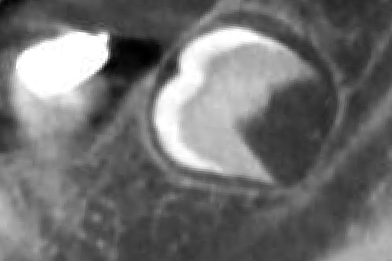

Опыт работы более 3 лет. Внимательный, вежливый доктор, специализируется на хирургической стоматологии. Лечит различные патологии челюсти: кисты, воспалительное заболевания ЧЛХ, удаляет сложные ретинированные зубы мудрости. Осуществляет дентальную имплантации, используя различные методики восстановления костной ткани.